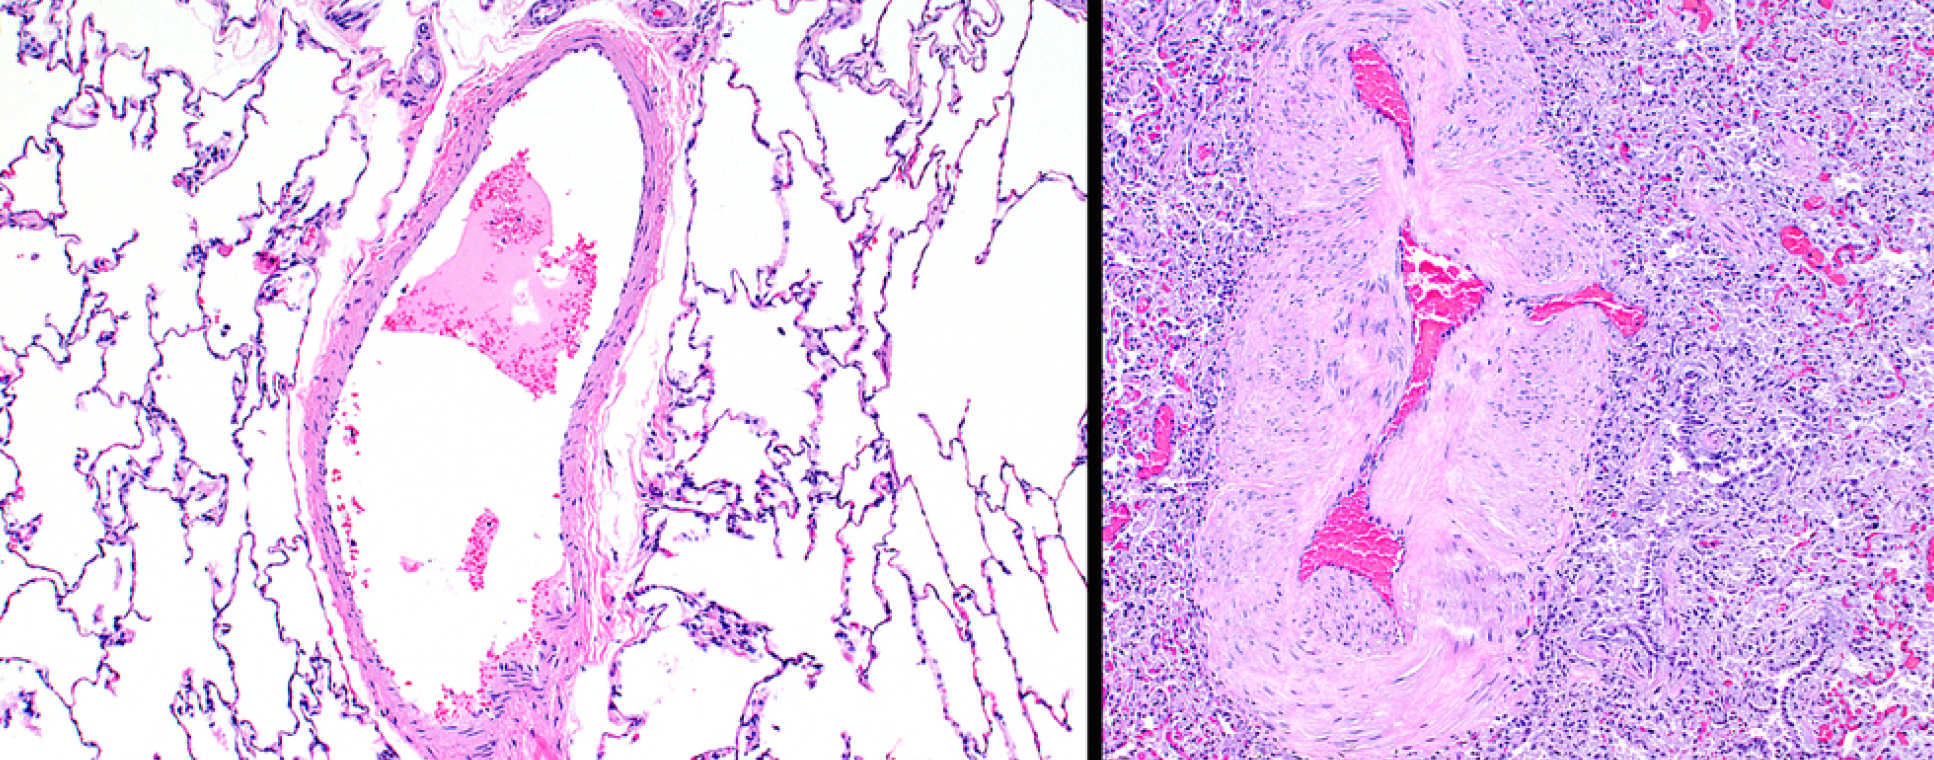

The evaluation of novel therapeutic agents in patients has become a challenge, as treatments move away from vasorelaxant drugs to agents that address the structural remodelling that characterises the disease. Advances in imaging offer a solution. The use of molecular imaging (e.g. PET-CT) to inform on the pharmacology of a drug in patients and cardiac magnetic resonance as a non-invasive tool for studying clinically meaningful drug response has been pioneered at Imperial.